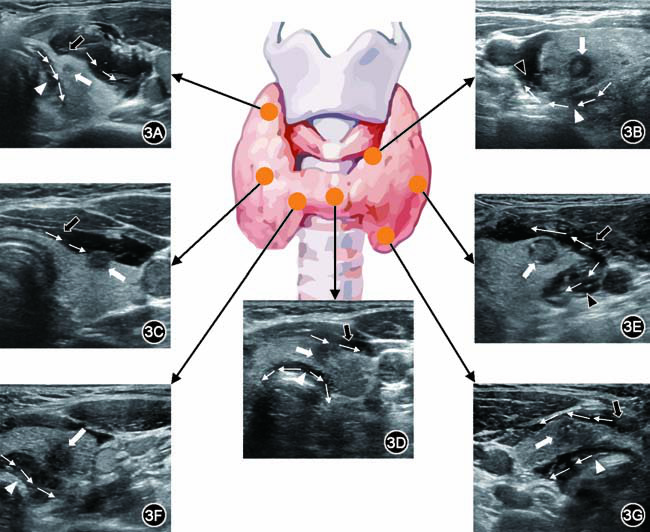

甲狀腺乳頭狀癌是一種預(yù)后較好的惡性腫瘤,以其惰性生物學(xué)行為為特征,具有良好的長(zhǎng)期生存率(>95%)。但近期發(fā)現(xiàn)部分亞型相較于經(jīng)典型甲狀腺乳頭狀癌具有更高的侵襲性和更不理想的預(yù)后。甲狀腺乳頭狀癌亞型是指具有甲狀腺乳頭狀癌的基本細(xì)胞核特征,但具有不同結(jié)構(gòu)、少見(jiàn)細(xì)胞質(zhì)特點(diǎn)或不同背景特征的甲狀腺乳頭狀癌。美國(guó)甲狀腺協(xié)會(huì)根據(jù)文獻(xiàn)中描述的生物學(xué)行為對(duì)甲狀腺乳頭狀癌變異體進(jìn)行了分類(lèi):1.預(yù)后較差的甲狀腺乳頭狀癌亞型1)鞋釘亞型。是一種較為罕見(jiàn)的中度分化的甲狀腺乳頭狀癌亞型,也被稱(chēng)作微乳頭變體,占所有甲狀腺乳頭狀癌的<2%,具有明顯的侵襲性和顯著的死亡率。具有復(fù)雜的乳頭狀結(jié)構(gòu),由核質(zhì)比增加的細(xì)胞緊密排列而成,細(xì)胞核位于頂端,產(chǎn)生表面隆起(鞋釘)這種高侵襲性或許與TERT基因突變有關(guān)。鞋釘亞型患者的腫瘤總是呈多灶性,58.3%左右的病例表現(xiàn)為雙側(cè)甲狀腺多發(fā)結(jié)節(jié),脈管侵犯的發(fā)生率為41.7%~71.4%。高達(dá)75%的患者在就診時(shí)發(fā)現(xiàn)淋巴結(jié)轉(zhuǎn)移,高達(dá)43.5%的患者發(fā)現(xiàn)遠(yuǎn)處轉(zhuǎn)移。超聲影像上表現(xiàn)為微小分葉的低回聲結(jié)節(jié),常伴有微鈣化和多灶淋巴結(jié)轉(zhuǎn)移。2)高細(xì)胞亞型。乳頭狀的高細(xì)胞變體是甲狀腺乳頭狀癌最常見(jiàn)的侵襲性變體,易發(fā)生甲狀腺外侵犯(包括包膜、血管、神經(jīng)及骨骼肌侵犯等)和淋巴結(jié)轉(zhuǎn)移等。由高為寬的2~3倍的細(xì)胞組成,顯示豐富的嗜酸性(嗜酸細(xì)胞樣)細(xì)胞質(zhì)。高細(xì)胞占比>10%便表現(xiàn)出更具侵襲性的特征,例如甲狀腺外延伸、血管淋巴侵犯、陽(yáng)性切緣和淋巴結(jié)轉(zhuǎn)移,并且這些特征的發(fā)生率隨著高細(xì)胞成分的增加而上升。超聲影像上一般表現(xiàn)為微分葉狀顯著實(shí)性低回聲結(jié)節(jié),伴有微鈣化,或伴有腺體外延伸和淋巴結(jié)轉(zhuǎn)移。3)柱狀細(xì)胞亞型。是臨床上罕見(jiàn)且發(fā)病年齡跨度大的甲狀腺癌,占所有甲狀腺乳頭狀癌的0.17%。通常體積較小、有包膜的CCV-甲狀腺乳頭狀癌表現(xiàn)為惰性,一般多見(jiàn)于年輕女性患者。嚴(yán)重的臨床癥狀,包括進(jìn)行性氣短、聲音嘶啞、喘鳴、氣管偏離、吞咽困難,腫瘤體積較大且呈彌漫性浸潤(rùn),伴有甲狀腺外侵犯、喉氣管侵犯和(或)頸淋巴結(jié)或遠(yuǎn)處轉(zhuǎn)移。超聲影像上,體積較小、有包膜的腫瘤表現(xiàn)為邊界清楚的低回聲結(jié)節(jié),伴或不伴有微鈣化,而侵襲性腫瘤表現(xiàn)為大的微葉狀低回聲結(jié)節(jié),通常突向包膜并且伴有腺體外延伸和頸淋巴結(jié)轉(zhuǎn)移。超聲影像上,體積較小、有包膜的腫瘤表現(xiàn)為邊界清楚的低回聲結(jié)節(jié),伴或不伴有微鈣化,而侵襲性腫瘤表現(xiàn)為大的微葉狀低回聲結(jié)節(jié),通常突向包膜并且伴有腺體外延伸和頸淋巴結(jié)轉(zhuǎn)移。4)實(shí)性細(xì)胞亞型。占成人甲狀腺乳頭狀癌的1%~3%,在年輕患者和有電離輻射暴露史的患者中更常見(jiàn)。從組織學(xué)上講,SV-甲狀腺乳頭狀癌除保留甲狀腺乳頭狀癌典型的細(xì)胞學(xué)特征以外,其主要特征是實(shí)性、小梁或島狀的成分累及腫瘤50%以上,其中腫瘤細(xì)胞形成超細(xì)胞巢。具有更高的肺和淋巴結(jié)轉(zhuǎn)移。超聲影像表現(xiàn)為伴有分散的微鈣化和大鈣化的不均勻低回聲。也有文獻(xiàn)報(bào)道超聲表現(xiàn)為境界清晰的低回聲結(jié)節(jié),周?chē)橛械突芈暵晻灐?)彌漫硬化亞型。少見(jiàn)的病理亞型,侵襲性強(qiáng)、轉(zhuǎn)移早、預(yù)后差,占所有甲狀腺乳頭狀癌的0.7%~6.6%。與經(jīng)典型甲狀腺乳頭狀癌相比,它多見(jiàn)于女性,并且呈現(xiàn)出年輕化的趨勢(shì)。甲狀腺(一葉或兩葉)彌漫性廣泛受累,通常不形成肉眼可見(jiàn)的腫瘤結(jié)節(jié),腫瘤的病理特征為廣泛鱗狀化生、大量砂小體、間質(zhì)纖維化和顯著的淋巴細(xì)胞浸潤(rùn)。由于其彌漫性,常需要與甲狀腺炎相鑒別。超聲特征包括正常甲狀腺實(shí)質(zhì)內(nèi)回聲不均勻,瘤體表現(xiàn)邊界不清的低回聲結(jié)節(jié),結(jié)節(jié)內(nèi)或結(jié)節(jié)外可見(jiàn)散發(fā)微鈣化(表現(xiàn)為“暴風(fēng)雪”),發(fā)生轉(zhuǎn)移的同側(cè)淋巴結(jié)同樣有微鈣化。2.預(yù)后較好的甲狀腺乳頭狀癌亞型1)濾泡亞型。除經(jīng)典型甲狀腺乳頭狀癌外臨床上最常見(jiàn)的甲狀腺乳頭狀癌亞型,約占所有甲狀腺乳頭狀癌的20%~30%,除具有甲狀腺乳頭狀癌典型細(xì)胞核特征(如毛玻璃樣變、核溝、核內(nèi)假包涵體等)外,此亞型結(jié)節(jié)70%~80%實(shí)性成分由濾泡結(jié)構(gòu)組成,且形態(tài)上缺乏乳頭狀結(jié)構(gòu)。最近有學(xué)者發(fā)現(xiàn)非包膜型侵襲性FV-甲狀腺乳頭狀癌惡性程度相對(duì)較高,且更加容易發(fā)生骨、肺轉(zhuǎn)移。超聲表現(xiàn),包膜內(nèi)型通常為邊界清晰的圓形或橢圓形等回聲或稍高回聲伴低回聲暈環(huán),而非包膜型更多表現(xiàn)為形態(tài)不規(guī)則的低回聲結(jié)節(jié)。2)包膜亞型。臨床上較為少見(jiàn)且預(yù)后良好,占全部甲狀腺乳頭狀癌的2.8%~3.8%。除具有經(jīng)典型甲狀腺乳頭狀癌細(xì)胞核特征以外,整個(gè)結(jié)節(jié)由纖維結(jié)締組織完全包裹。有學(xué)者根據(jù)其包膜內(nèi)組成將其分為普通乳頭型、濾泡型、腺瘤型3種,并且由臨床數(shù)據(jù)發(fā)現(xiàn)普通乳頭型甲狀腺乳頭狀癌的生物學(xué)行為更加貼近經(jīng)典型甲狀腺乳頭狀癌。在超聲表現(xiàn)上,包膜濾泡型甲狀腺乳頭狀癌表現(xiàn)為邊界清晰光滑、圓形或橢圓形的等回聲,包膜乳頭型甲狀腺乳頭狀癌多表現(xiàn)為邊界清晰、形態(tài)不規(guī)則的低回聲,伴或不伴有鈣化。由于有完整的纖維性包膜包裹,結(jié)節(jié)周邊可見(jiàn)明顯的聲暈,可與經(jīng)典型甲狀腺乳頭狀癌區(qū)分開(kāi)。3)篩狀-桑椹胚亞型。是非常罕見(jiàn)且預(yù)后較好的惰性甲狀腺乳頭狀癌亞型之一,約占全部甲狀腺乳頭狀癌的0.2%。常見(jiàn)于家族性腺瘤性息肉病,但也存在少數(shù)散發(fā)病例。表現(xiàn)為多灶性結(jié)節(jié)和逐漸增大的無(wú)痛性頸部腫塊,而散發(fā)性則表現(xiàn)為單發(fā)的甲狀腺結(jié)節(jié),偶爾可能具有侵襲性。其鏡下特征除具有典型的甲狀腺乳頭狀癌細(xì)胞核特征之外,癌細(xì)胞呈篩狀和桑葚胚狀。超聲影像特征為界限清楚的圓形或橢圓形、外切、混合回聲或低回聲實(shí)性結(jié)節(jié),不伴有低回聲暈環(huán)或鈣化,部分結(jié)節(jié)可表現(xiàn)為囊性改變或微鈣化。4)Warthin瘤樣亞型。罕見(jiàn)的甲狀腺乳頭狀癌亞型,約占全部甲狀腺乳頭狀癌的0.2%~1.9%,因形態(tài)學(xué)改變類(lèi)似涎腺Warthin瘤得名,此亞型不僅具有甲狀腺乳頭狀癌特征的細(xì)胞核特征如毛玻璃樣核、核溝、包涵體及典型的乳頭狀結(jié)構(gòu),其腫瘤細(xì)胞胞質(zhì)表現(xiàn)為強(qiáng)嗜酸性,細(xì)胞間質(zhì)存在顯著的淋巴細(xì)胞和漿細(xì)胞浸潤(rùn),并且常常伴有橋本甲狀腺炎的背景。超聲影像中,由于實(shí)質(zhì)回聲常不均勻,易被誤診為局灶性甲狀腺炎癥和良性結(jié)節(jié),超聲特征分別為實(shí)性成分、低回聲和“縱橫比>1”。顯示邊界清晰,有囊性成分。不均勻?qū)嵸|(zhì)回聲,并伴有慢性淋巴細(xì)胞性甲狀腺炎。